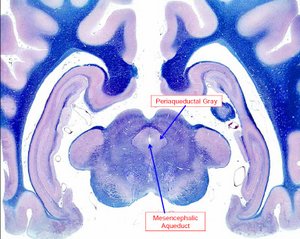

detalle histológico de un corte axial del mesencéfalo

El mesencéfalo o encéfalo medio se originan el nervio oculomotor (III) y troclear (IV), y contiene el acueducto mesencefálico por el que circula el LCR.

La materia gris periacueductal juega una importante función en la modulación del dolor.